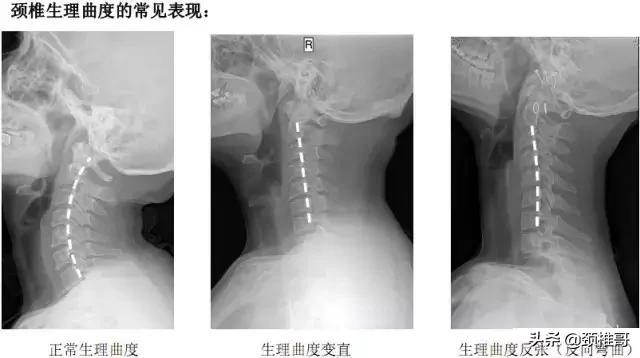

颈椎反弓(比强直更为严重的颈椎疾病)相比强直的颈椎,反弓的颈椎曲度是个反C型,而正常曲度应该是正C型。颈椎有正常的生理弯曲,如果没有生理弯曲,甚至向相反的方向弯曲,称为反弓。